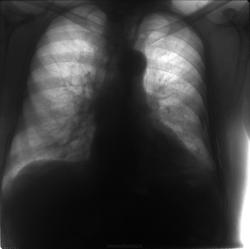

Вот такой случай попался сегодня от коллег из районного центра.

Вчера упал, поломал ребра, пошел домой. Сегодня шею эмфиземой раздуло до удушья. Вопрос поставили есть ли тут пневмомедиастинум? И может ли воздух проникать в ткани шеи только из средостения или есть и другие пути? Ответил что пневмомедиастинум есть. В какой-то статье по КТ читал, что воздух в шее может появится только из средостения. Обсуждаем

Что-то пневмомедиастинума не рассмотрел. В прямой. Боковую косую бы - было бы дело. А так - можно и на КТ!) Я тут, често признаюсь, даже пневмоторакса толком не разглядел. А он же должен быть... где-то. Отчего же в грудной полости у пациента такой беспредел?.. Насчёт распространения - отчего же не может. Подкожная эмфизема хорошо распространяется. И на шею под кожей быстро залазит. Бывало. Медиастинум был не затронут - точно, делали и КТ - но эмфиземой шея была затронута. Доказательств, то бишь снимков у меня, к сожеланию, с собой нет.(

Перелом 4-5-6-7-8 рёбер слева с малым гидротораксом, дренаж в 6 межреберье. Всё остальное на фоне выраженной подкожной и межмышечной эмфиземы - эфемерно и неубедительно.

Обратил внимание на воздух справа (синие стрелки). Ну и слева парамедиастенально (красные стрелки) расценил как смещенную воздухом плевру. Пневмоторакса слева, по крайней мере, просто не видно, возможно какой-то минимальный есть. Предположу, что воздух распостраняется по обеим путям, которое описаны коллегой Любовь С. ) Пациент после второго снимка отправлен сразу в торакальную хирургию, на месте больше ничего не делали. Постараюсь узнать дальнейший ход событий.

Согласен с Любовью, распространение воздуха хорошо описала. От себя добавлю: месяц назад госпитализировали больного после ДТП, перелом 1 ребра, а подкожная эмфизема была от шеи до мошонки, все по левой половине. По второй рентгеногамме кажется, что тень которую модно принять за пневмомедиастинум, является частичным ателектазом нижней доли.